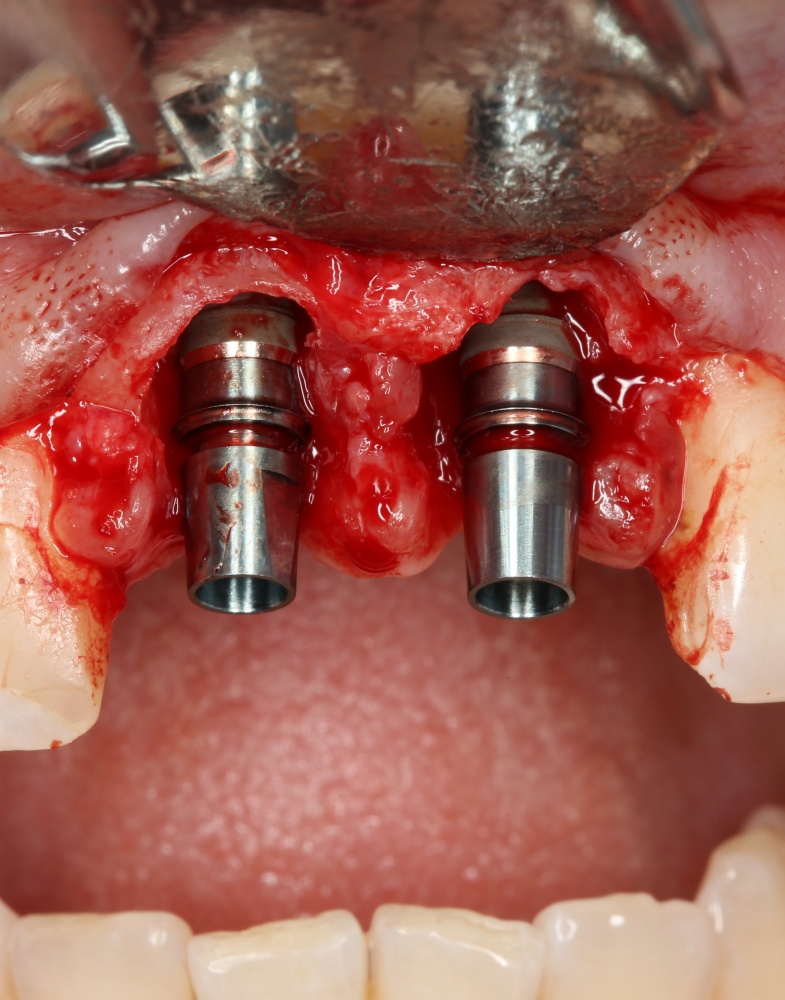

Рекомендации по установке имплантов. Для всех. Часть V.